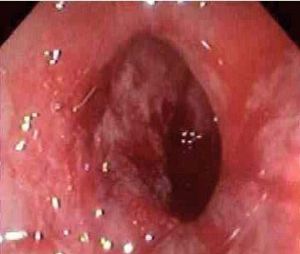

老年人缺血性結腸炎實例圖老年人缺血性結腸炎通常是自發性的 ,沒有特異性的症狀或體徵其臨床表現由於其嚴重性、累及範圍、缺血損害發生的快慢、腸壁對缺氧的耐受程度不同而不同。通常可見60歲以上的老年患者,以往並無結腸疾病史的,而突然出現急腹症的表現 。其最一致的症狀和體徵是:腹痛、腹瀉及便血鶒。這種失血通常量很少,疼痛發作急驟,為痙攣性 ,常常局限於左下腹;大便急,並常伴有疼痛;可能出現繼發與腸梗阻的症狀,如厭食、噁心、嘔吐腹部檢查常可見與缺血結腸相對應部位的腹脹和觸痛。一般沒有明顯的發熱,直腸檢查常可見帶血的大便。心血管檢查一般無陽性發現。

2.纖維結腸檢查 對本病的早期診斷有重要價值,但應注意壞疽型不宜做結腸鏡檢查。其鏡下表現為:

(1)急性期:起病72h以內 ,黏膜充血、水腫,多見散在出血點淺表糜爛,約半數可有淺表潰瘍,病變呈節段性分布界限清楚;活檢可見炎細胞浸潤鶒,小血管內纖維素樣血栓形成腺管破壞及灶性出血

(2)亞急性期:起病72h至7天,可見典型縱行潰瘍形成,並可見明顯的炎性滲出物;活檢可見組織壞死及肉芽修復。

(3)慢性期:起病後兩周至兩個月,鏡下僅見輕度炎症改變無特徵性。活檢整體退行性變纖維組織及肉芽組織增生並可見較特異的含鐵血黃素沉著